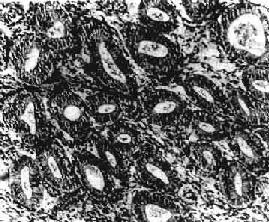

图13-6 子宫内膜增生症 腺体明显增多、大小不一、分布不均,腺上皮多层,间质增生,排列紧密 【临床病理联系】 子宫内膜增生症的子宫不规则出血是由卵巢滤泡不排卵所致。由于卵巢持续分泌雌激素,一方面引起子宫内膜增生,另方面抑制垂体前叶卵泡刺激素的分泌,终致卵泡因失去卵泡刺激素的支持而发生退化,雌激素分泌因而急骤下降,增生的子宫内膜由于雌激素突然不足而发生坏死脱落,引起子宫出血。 有些功能性子宫出血的病人,偶尔在更年期前或更年期可见到分泌期内膜,有人认为系更年期前激素不平衡,垂体促性腺激素产生过度或黄体功能过盛所致。临床可有月经过多表现,称排卵性功能性子宫出血。

一、子宫内膜增生症子宫内膜增生症(endometrial hyperplasia)临床表现为功能性子宫出血,主要症状为月经不规则、经期延长和月经量过多。大部分病人发生于更年期或青春期。其发生与卵巢雌激素分泌过多而孕酮缺乏有关。 【病变】 肉眼观,一般可见子宫内膜普遍增厚,可达0.5~1cm,表面光滑,柔软,也可呈不规则形或息肉状。镜下,可分4种类型:①单纯型,子宫内膜腺体及间质均增生,腺体明显增多、大小不一、分布不均(图13-6)。偶见腺体扩大成囊,腺上皮细胞呈柱状,缺乏分泌,往往排列成假复层。核分裂像常见。间质细胞排列紧密。②囊腺型,以增生腺体呈明显囊性扩张为特征。典型病例肉眼可见在增厚的内膜中有散在小孔形成,因此称之为瑞士干酪样增生。镜下,内膜腺体形状多样,大小极不一致,小者如增生早期的腺体,大者直径可为小的数倍至数十倍,大小腺体皆衬以假复层高柱状或立方上皮,并缺乏分泌现象。间质细胞丰富,胞浆少,核浓染。③腺瘤样型,以腺体增生而密集排列和间质稀少为特征,腺体数量远比前两型为多,结构也更加复杂,腺上皮向腺腔内呈乳头状或向间质呈出芽样增生。间质稀少。腺上皮细胞为高柱状,假复层,核空泡状,核分裂像常见,但无明显异型性。④不典型增生,组织结构与腺瘤样增生相似,腺体拥挤并呈不规则形、分支状或出芽样增生,间质明显减少,同时出现腺上皮细胞的异型性,细胞核大,染色质粗,核仁明显,上皮复层,失去极性,常见核分裂像。子宫内膜不典型增生有时很难与高分化腺癌鉴别,主要鉴别点是前者不见间质浸润。有人认为它是子宫内膜腺癌的癌前变化。